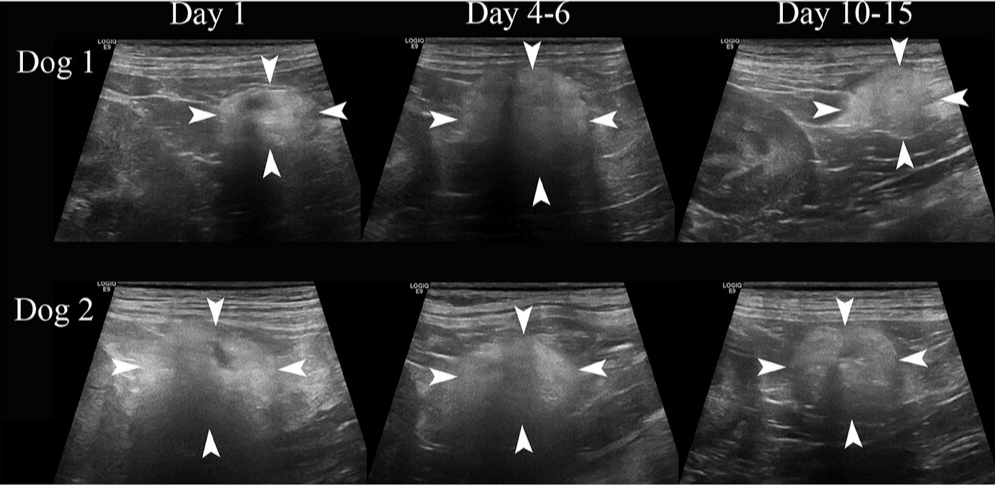

즉, 정상적으로 수술되어 부작용 없이 잘 치유된 자궁축농증 개에서 수술 이후 보이는 변화상에 대한 논문이다. 영상논문이라 초음파만 말할 것 같지만 혈액상의 변화도 같이 제시되어 있으니 참조해 보자.